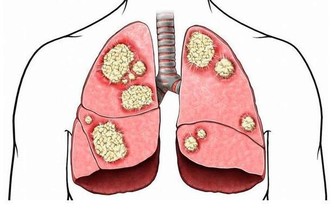

中醫理論認為: 氣血不通暢,則會疼痛。而其主要有兩個原因,一是老人年本身體虛,自身調節能力較弱,再加如果受了風寒,氣血則會更不通暢。如果不及時調整,氣血不通之後,隨之而來的比如心臟病、等各種器質性的病變。

以下圖片來源 西醫認為: 缺鈣和脊椎的形變是最大的禍首。如果不及時治療,那麼,隨著鈣質的繼續流失、包括頸椎和腰椎兩大人體主要部位的形變,隨之而來的由骨折引起的死亡,腰椎、頸椎引起的腦供血不足和癱瘓等等,也會慢慢接近。